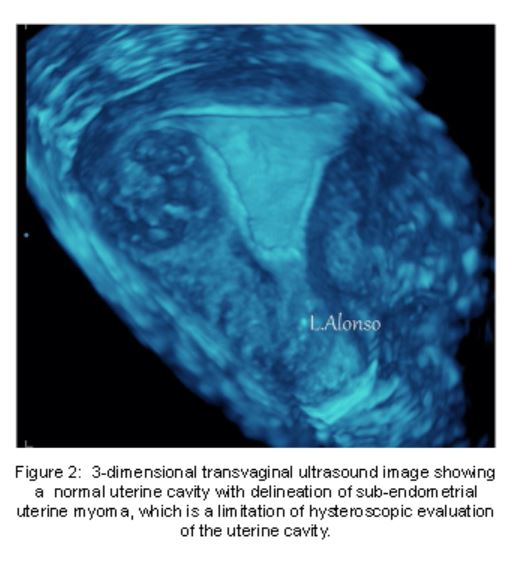

With 3DTVUS imaging, uterine cavity evaluation is enhanced above gray scale 2DTVUS. The 3D scan simultaneously displays three perpendicular image planes creating a detailed image construction of surface detail. One advantage of 3DTVUS over HS is the evaluation of sub-endometrial regions of the uterus as well as the endometrial cavity (Figure 2) . Hysteroscopy, however, still more accurately identifies submucous myomas.